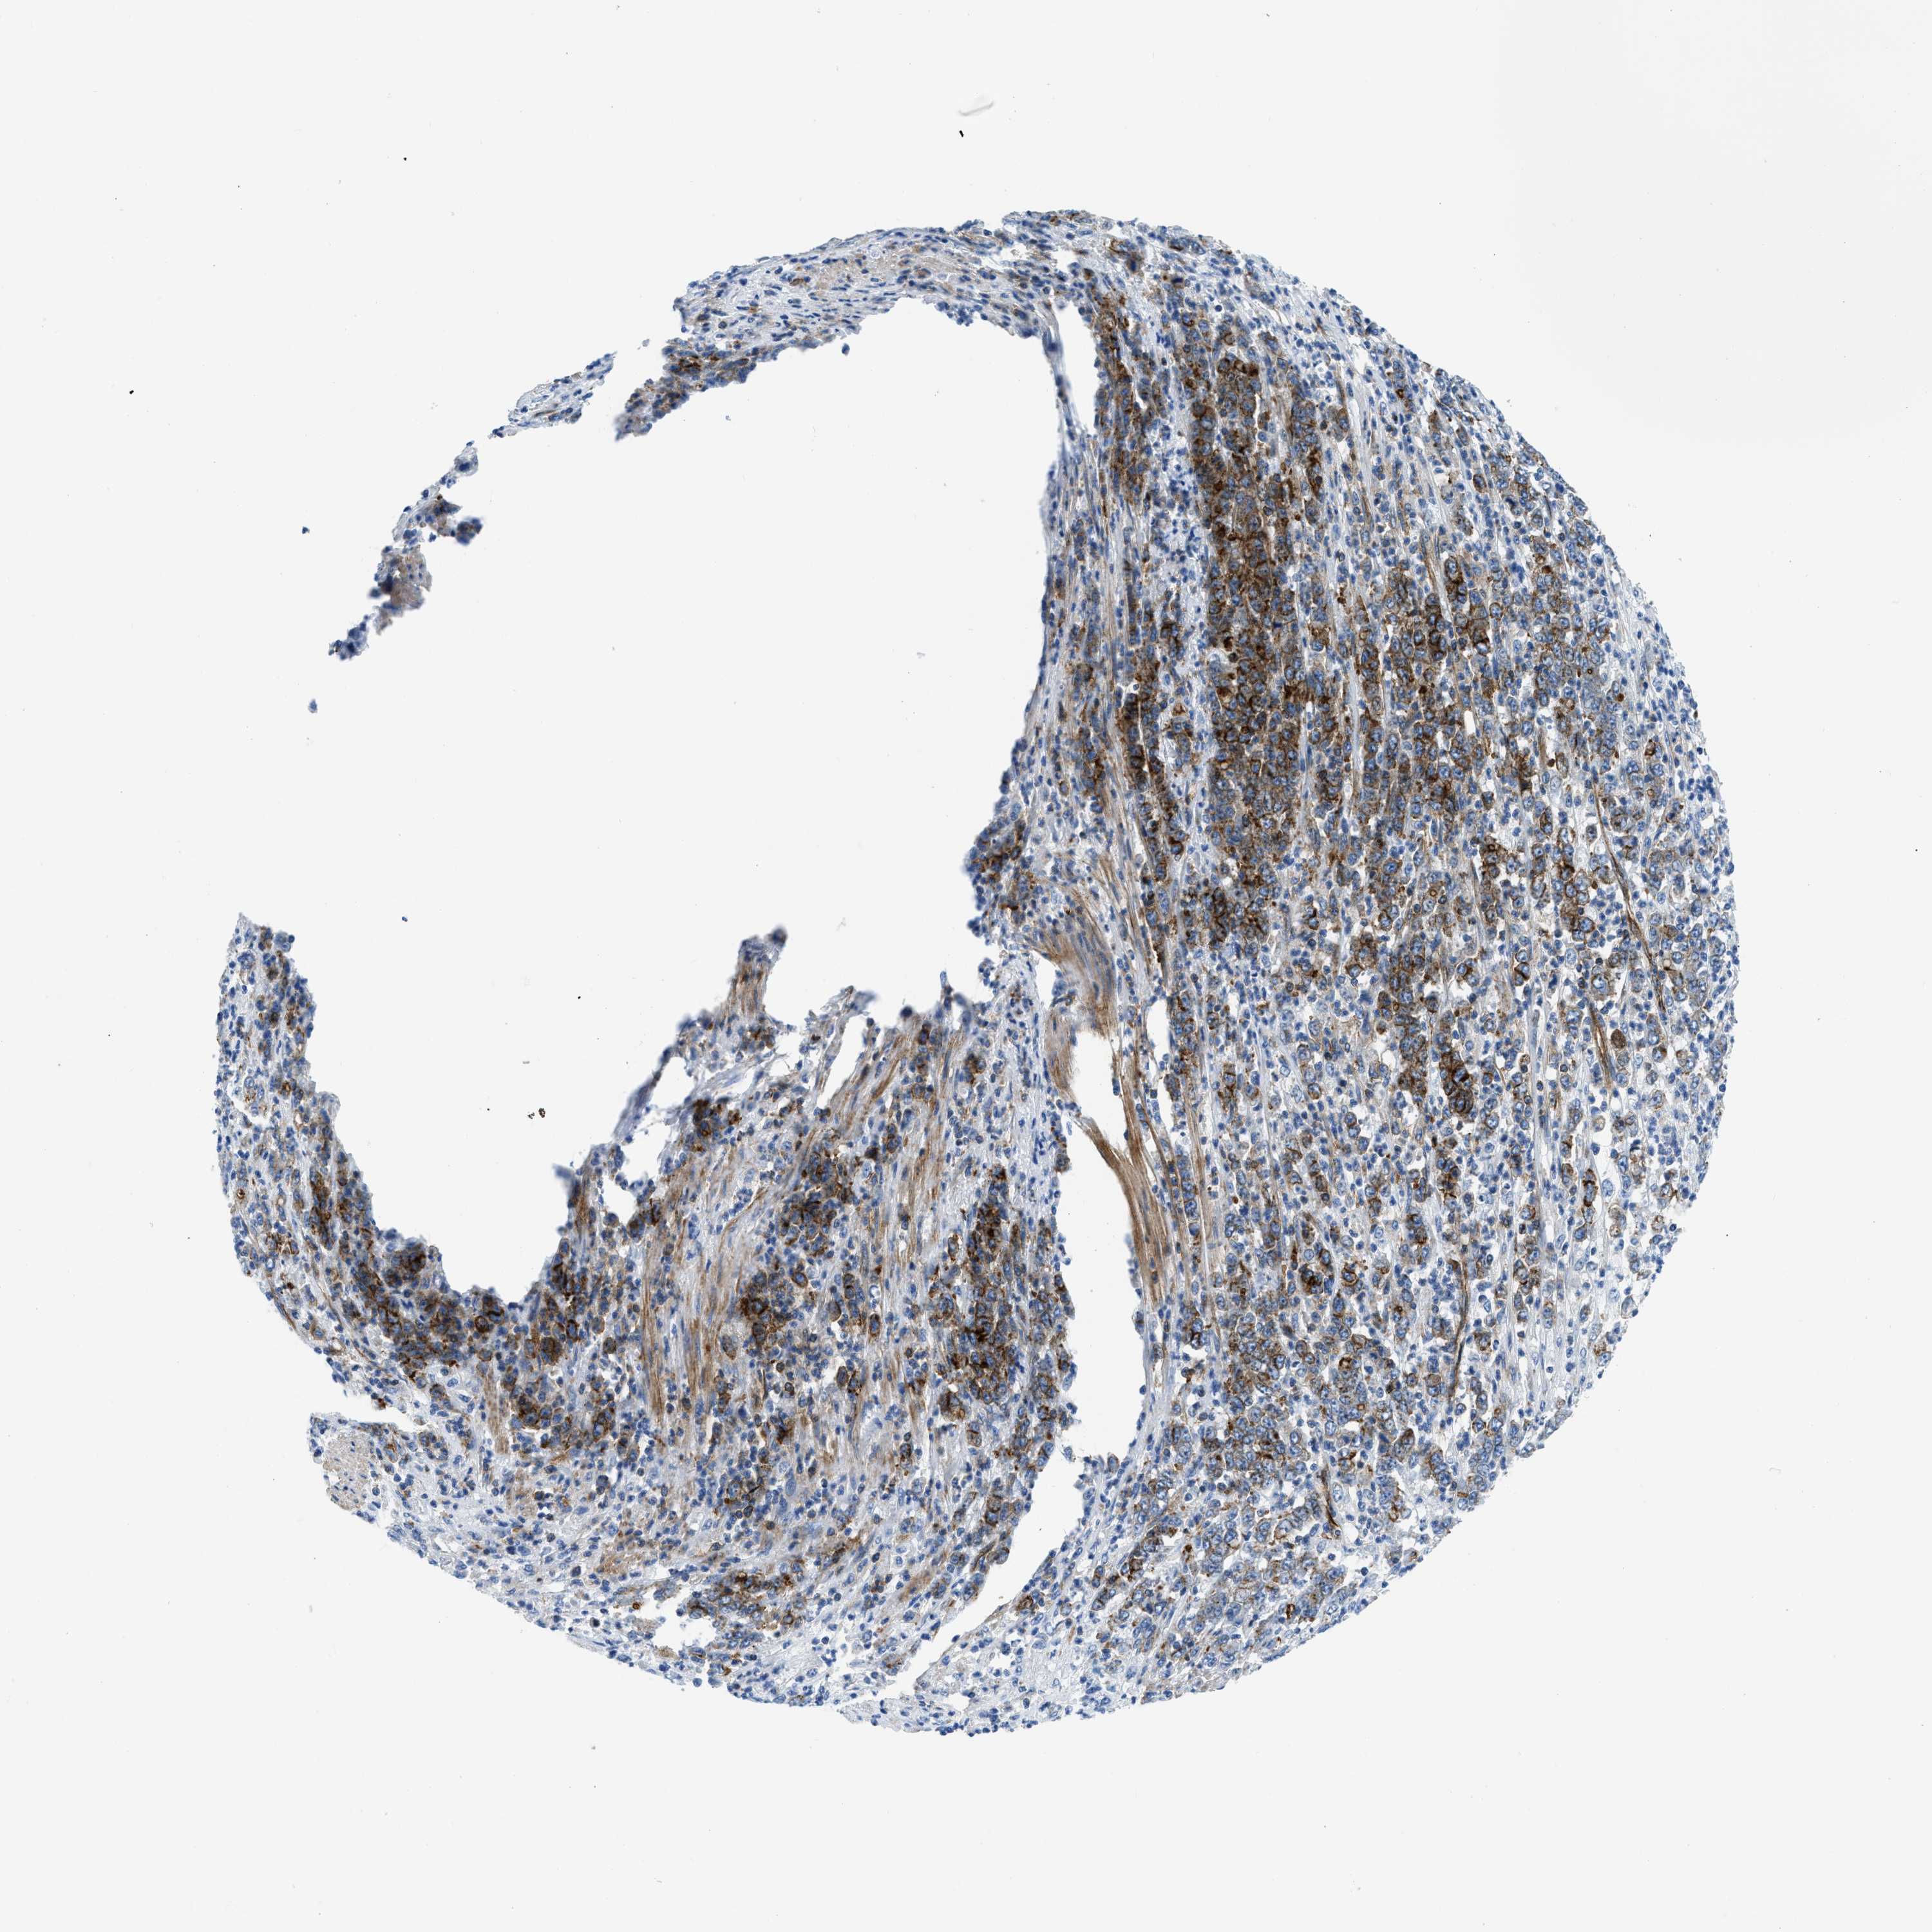

STOMACH CANCER - Protein expressioni

A mouse-over function shows sample information and annotation data. Click on an image to view it in a full screen mode. Samples can be filtered based on level of antibody staining by selecting one or several of the following categories: high, medium, low and not detected. The assay and annotation is described here.

Note that samples used for immunohistochemistry by the Human Protein Atlas do not correspond to samples in the TCGA dataset.

Antibody stainingi

Antibody staining in the annotated cell types in the current human tissue is reported as not detected, low, medium, or high, based on conventional immunohistochemistry profiling in selected tissues. This score is based on the combination of the staining intensity and fraction of stained cells.

Each image is clickable and will lead to virtual microscopy that enables deeper exploration of all samples and also displays staining intensity scores, fraction scores and subcellular localization as well as patient and tissue information for each sample.

Antibody CAB016787

Staining

High

Medium

Low

Not detected

Intensity

Strong

Moderate

Weak

Negative

Quantity

>75%

75%-25%

<25%

None

Location

Nuclear

Cytoplasmic/membranous

Cytoplasmic/membranous,nuclear

Adenocarcinoma, High grade